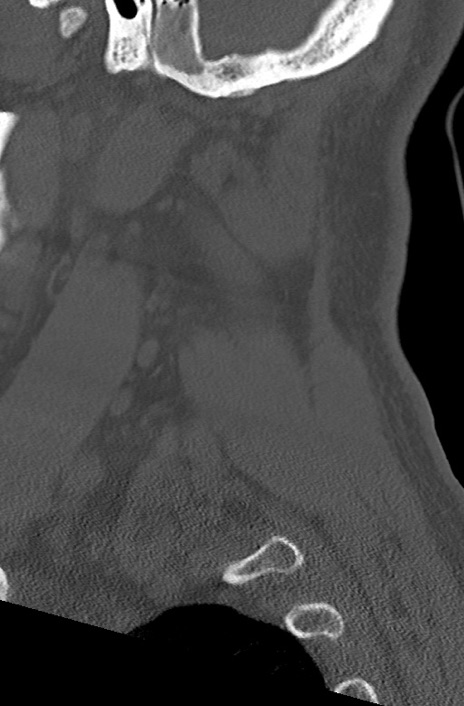

頚椎CT

矢状断像と横断像